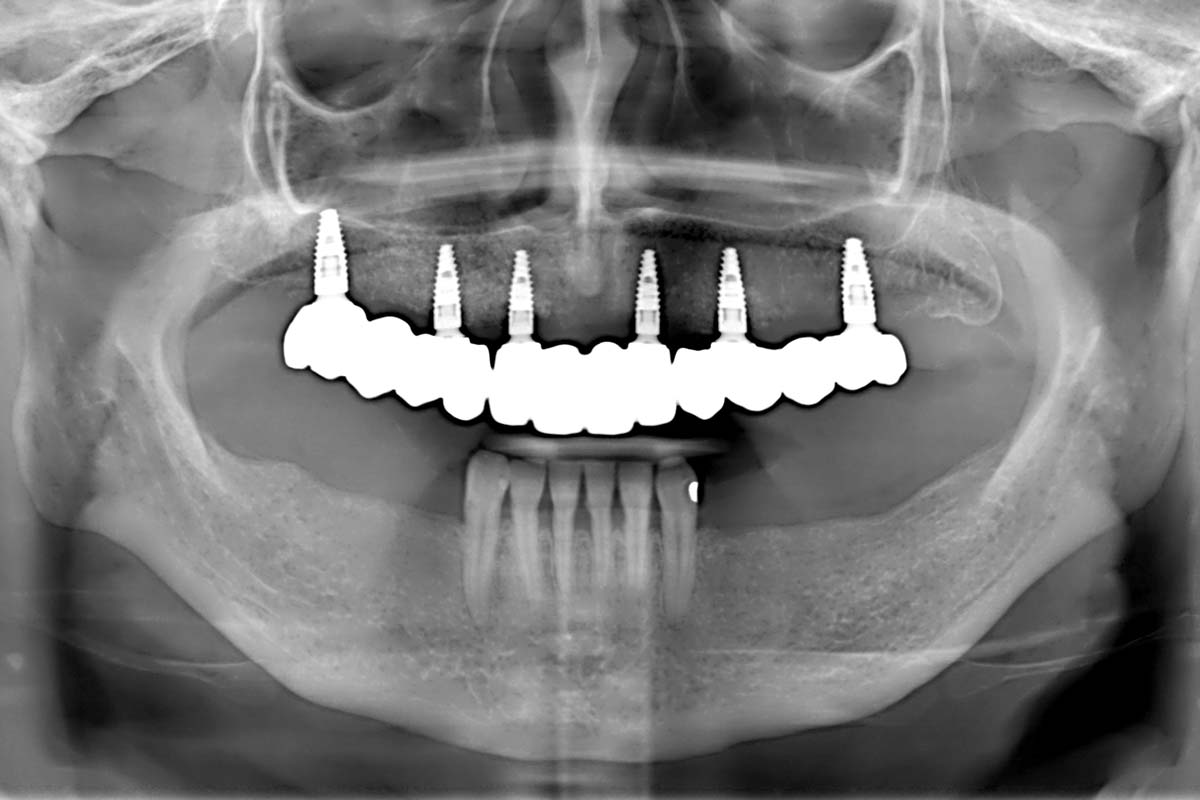

Full arch GBR using cerabone®, maxgraft® and Jason® membrane with simultaneous implantation of 6 Straumann® implants - Dres. A. Signorio and G. Molina